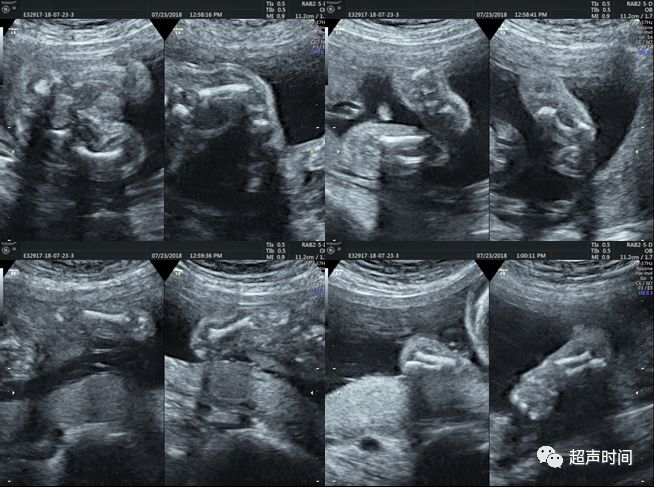

胎头明显增大,前额突出(图 1)。胸腔狭窄,胸围明显缩小,心胸比值明显增大,肋骨短小,腹围明显增大(图 2)。股骨、胫腓骨及肱骨、尺桡骨均明显缩短,骨干明显弯曲,股骨干骺端粗大呈「电话听筒」状(图 3)。手、足未见异常。

图 3 胎儿四肢表现